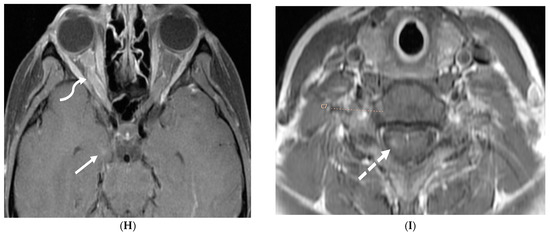

Figure 20.

Axial T2 (A), axial DWI (B), axial SWI (C) and axial T1 post contrast (D): 4-year-old girl with acute lymphoblastic leukemia, pancytopenia and fever. Treatment started one week before with asparaginase. There is prominently T2 hyperintensity and swelling of the gyri involving the medial aspect of the left parietal occipital cortex (arrow). Multiple small foci of T2 hypointensities are identified within the involved region with corresponding blooming on the susceptibility indicating hemorrhage (curved arrow) and peripheral rim of true restricted diffusion (dashed arrow). Postcontrast images show pachymeningeal and LME in the involved region (open arrows). Features are concerning for fungal infection. Pathology revealed Rhizomucor pusillis (thermophilic fungus).